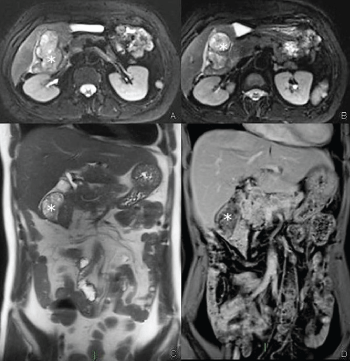

Figure 5: Contrast enhanced MRI: Lesion of the gastric fundus T2 fat saturated axial image (A) and T1 fat saturated post-contrast image (B) showing a paraaortic lesion with multicystic appearance (arrows). View Figure 5

Figure 6: Contrast enhanced MRI: Paraduodenal lesion T2 fat saturated axial image (A,B), coronal HASTE image (C), post-contrast coronal T1 fat saturated (D) showing a well-defined lesion with multicystic appearance (asterisks) with thick rim-like enhancement well visible in the delayed phase (in D). View Figure 6